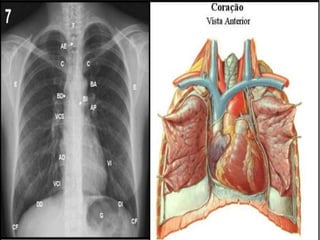

CORAÇÃO

É um órgão muscular ímpar e

mediano, com a forma de um cone

truncado, situado dentro da caixa

torácica entre os dois pulmões, no

mediastino anterior. Repousa sobre

Cavidade torácica

• Sob o esterno, por diante da coluna vertebral

e do esôfago

• Sobre o diafragma

• Entre dois conjuntos pleuro-pulmonares

• Tem seu ápice ligeiramente voltado para a

esquerda e para frente, tocando a parede

torácica

• Peso médio de 5g/Kg no adulto, com altura

entre 13 e 15 cm, largura de 9 a 10cm e

espessura em torno de 6 cm

Localização

• Paredes: pericárdio, epicárdio, miocárdio,

endocárdio

• Câmaras superiores: átrios direito e esquerdo

• Câmaras inferiores: ventrículos direito e

esquerdo

• Valvas internas: tricúspide, mitral, pulmonar e

aórtica

• Artérias e veias coronárias

• Vasos: Aorta, Artéria Pulmonar, VCS, VCI, Veias

Pulmonares

• Sistema de formação e condução do estímulo

elétrico

Estruturas